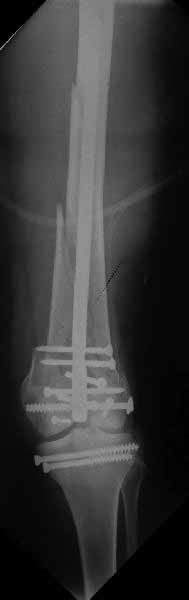

Коллеги, извиняюсь за задержку с результатом. Через медиальную артротомию обнажили н/3 бедра, отрепонировали внутренний мыщелок, затем по нему сопоставили суставную поверхность бедра с латеральным мыщелком.

Больная выписана в ортезе с регулируемым углом сгибания в колене, с рекомендациями через 3 нед. удалить спицы и начать разрабатывать сустав.

По прямому снимку репозиция удалось, поздравляю! А с латеральной стороны подозрение на флексионный компонент латерального мыщелка остается, а снимок получился косым, надо было бы повторить.

Выбор имплантов не совсем удачный, подкожно выступающие болты в мыщелках вскоре могут привести к проблемам. Вместо солитарной фиксации болтом-стяжкой дистально можно было бы добавить пару винтов, которые создали бы ротационную стабильность и межфрагментарную компрессию.

Возможно, есть скрытый замысел, неочевидный для нас - не понятны латерально оставленные спицы. Спицы возможный очаг вторичного осложнения, и, тем более у взрослых, тонкие спицы не создают адекватную фиксацию.

Djoldas,скрытого смысла в спицах нет. Без них латеральный мыщелок получается фиксированным только к медиальному, который, в свою очередь, фиксирован к проксимальному отломку. Соответственно латеральный мыщелок не фиксирован к бедру. Спицами мы попытались создать какую-никакую-стабильность латерального мыщелка относительно проксимального отломка бедра.

Болт-стяжка, на мой взгляд, создает не меньшую межфрагментарную компрессию чем винты. Не понял относительно ротационной стабильности винтов.